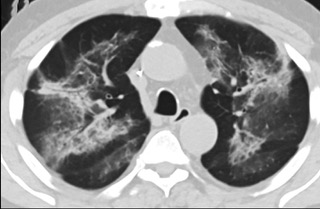

中、下肺軸位CT平掃顯示毛玻璃樣混濁伴胸膜下保留(箭頭)。(同一病人CT影像)